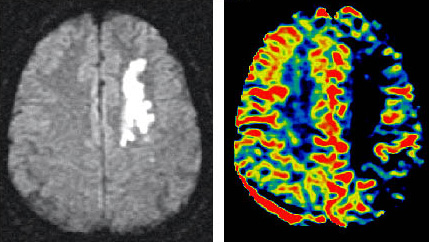

Acaba de publicarse en el New England Journal of Medicine un estudio randomizado realizado en 112 pacientes de 60 años o mayores (entre 61-82 años), con diagnósticos de infartos hemorrágicos malignos afectando a la arteria cerebral media.

A las 48 horas del ictus se asignaron los pacientes a dos grupos, uno de ellos ingresados en unidad de cuidados intensivos (grupo control) y otro grupo fue sometido a hemicraniectomía (intervención neuroquirúrgica de evacuación de la hemorragia).

Por lo tanto parece ser beneficioso que se realice la intervención neuroquirúrgica en las primeras horas tras el diagnóstico de un ictus hemorrágico maligno para evacuar el hematoma en pacientes de 61 años o mayores, ya que esto ayudaría a disminuir el grado de discapacidad y mortalidad.